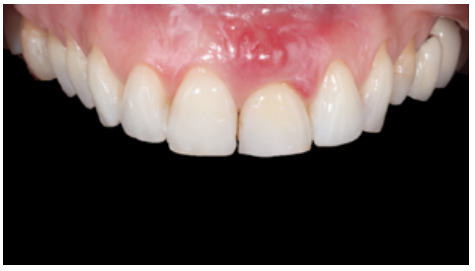

At the intraoral level, a mid-smile line and fine gingival biotype was observed, accompanied by gingival recessions at the level of the upper right central incisor (URCI), as well as in the first, third and fifth sextant teeth. There was slight crowding in the lower anterior region and evidence of multiple dental treatments, such as root canals and osseointegrated implants (OII).

Erythematous mucosa was observed In the ULCI region, accompanied by inflammation of the apical region of the tooth at the level of the attached gingiva, suspected to be due to a periapical abscess following infection of the tooth (Figure 1). The ULCI had great mobility due to a radicular fracture not observed on clinical examination.